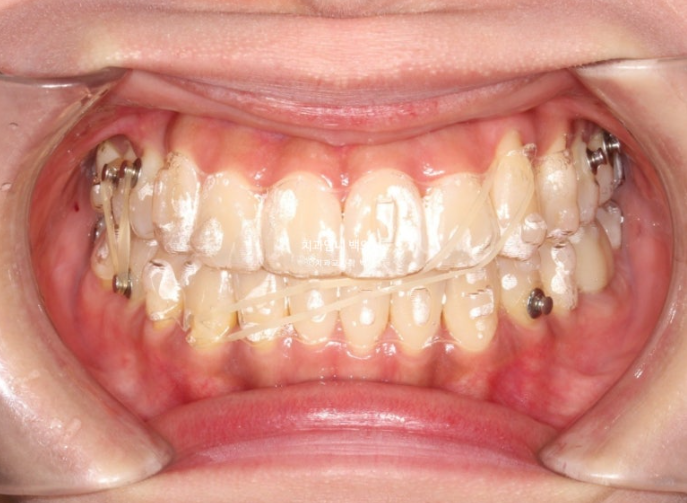

어금니 교합이 뜨는 부분과 먼저 닿는 부분들을 개선하고자 재제작에 들어갑니다.

재제작 추가장치 갯수는 17개 나왔습니다.

어금니 교합 안정화와 중심선 개선을 위해 추가장치에서는 고무줄 처방이 들어갑니다.

25년 1월부터 25년 3월까지 장치를 모두 낀 후 모습입니다.

총 치료기간은 1년 6개월입니다.